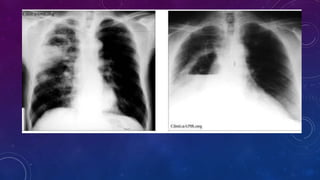

DIAGNOSTICO

ADICIONAL

DIAGNOSTICO DIFERENCIAL

Periodo inicial:

• Neumopatías agudas (neumonías, tuberculosis, infarto del pulmón)

• Bulas pulmonares infectadas

Periodo de vómica y supuración

• Bronquiectasia

• Neoplasia abscedada

• Tuberculosis cavitaria

• Quistes aéreos congénitos infectados.